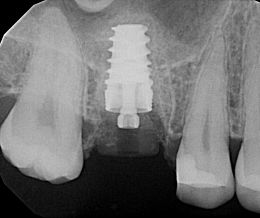

Preoperative 3D imaging is helpful in visualizing the patient’s anatomy and screening the ideal candidate. Since there is limited bone available, a dental implant with aggressive threading is important to obtain good primary stability. Typically, the socket is larger than the diameter of the dental implant and a bone graft is required to fill the space. A large stock, or customized healing abutment, can then be used to contain the bone graft and allow for ideal soft tissue healing.